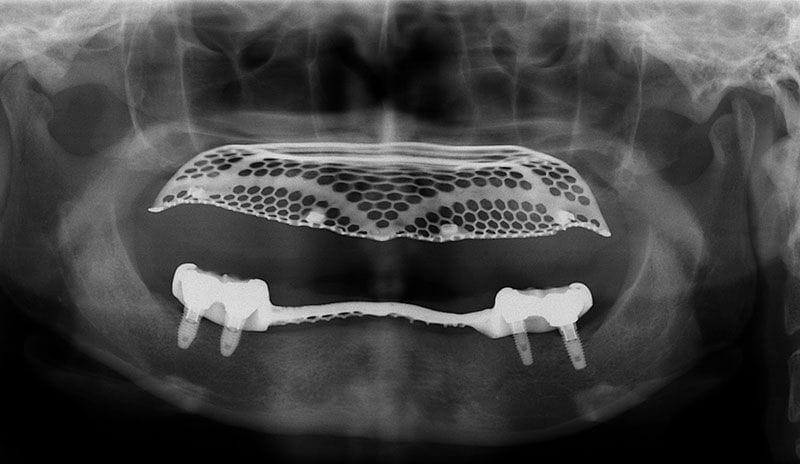

許多人缺牙多年後才想要植牙,但此時齒槽骨已萎縮,少了堅固的骨頭做為牙根的支撐當然不會穩固。因此可以把補骨想成幫牙根打地基,有了堅硬的地基再植入人工牙根,植牙效果才會穩定耐用。